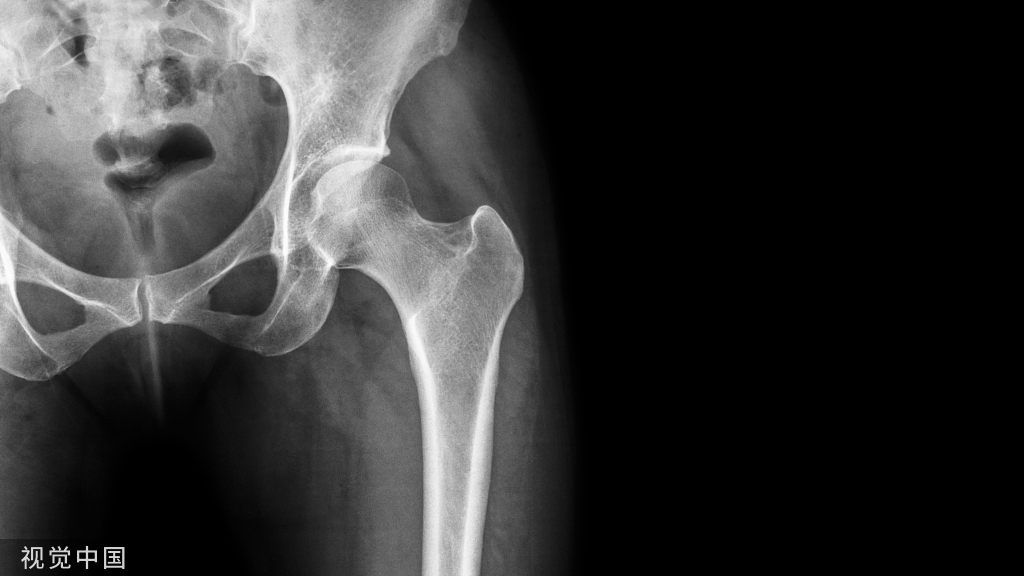

上颌后牙区第一磨牙是缺失频率较高的牙位(图1A),由于各种原因会导致该位点的牙槽骨高度不足。该病例为47岁男性患者,A6缺失,不吸烟,既往史无特殊,健康状态良好。患者要求种植修复,避免伤及邻牙。

术前CBCT示剩余牙槽骨高度约3mm,近远中距离约10mm,宽度大于8mm,上颌窦内清澈无炎症,上颌窦底黏膜约2mm(图1B,C)。为保证植骨效果,拟进行上颌窦侧壁开窗外提升并同期植入种植体。

图1 A6缺失,CBCT示剩余牙槽骨高度3mmA.口内观;B.矢状面;C.冠状面